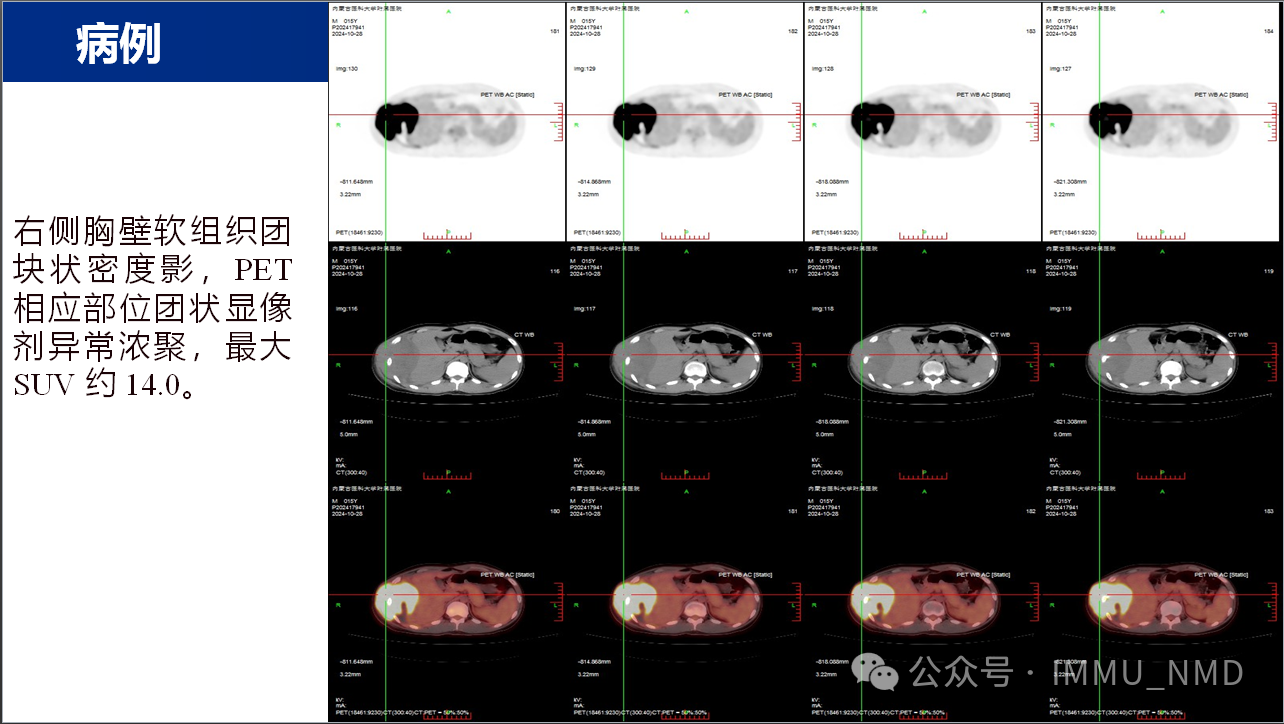

2025年2月27日上午,由核医学科党支部和内蒙古自治区医学会核医学分会青年委员会共同组织的“核先锋”青年医师疑难病例读片会第二十七期暨内蒙古自治区医学会核医学分会青委会青年医师疑难病例读片会第七期于线上腾讯会议及线下核医学科示教室成功举办。参加线下读片会的有党支部的全体党员医生及非党员医生、研究生、规培生、进修生,参加线上读片会的有青委会多名医生,读片会由张国建教授做最后总结。